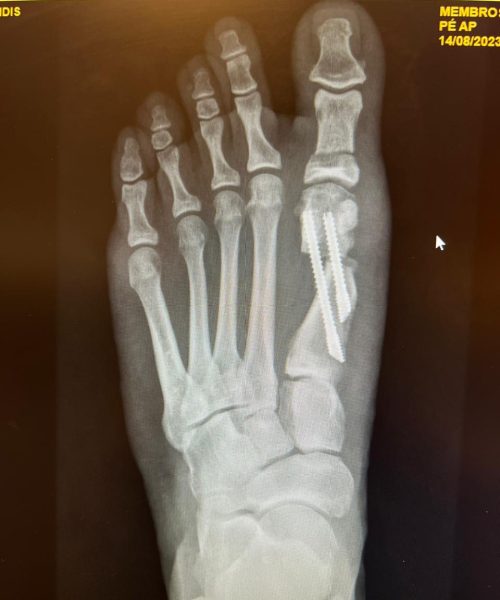

A cirurgia minimamente invasiva é uma abordagem cirúrgica que utiliza pequenas incisões e instrumentos especializados para tratar condições no pé e tornozelo, minimizando danos aos tecidos circundantes.

A cirurgia minimamente invasiva é indicada para pacientes que buscam uma recuperação mais rápida e menos desconforto pós-operatório. É especialmente benéfica para casos selecionados de deformidades e lesões nos pés e tornozelos. de alguma condição que afeta a articulação do tornozelo, como lesões de cartilagem, inflamações, corpos livres, impactos, instabilidade ou artrose .

A cirurgia é realizada através de pequenas incisões, geralmente com o auxílio de um endoscópio. Isso permite ao cirurgião tratar a condição alvo com precisão, reduzindo o trauma aos tecidos circundantes.